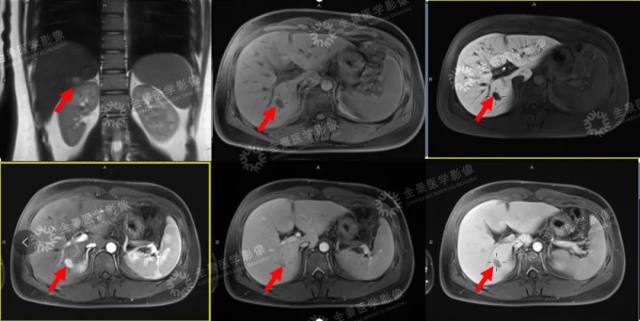

普美显 MR 增强影像资料

影像学诊断

肝右后叶下段一枚异常信号结节,T1WI 呈稍低信号,T2WI 呈稍高信号,DWI 呈稍高信号,增强扫描肝动脉期呈明显强化,门静脉期及延迟期快速减退,肝胆期呈低信号。

明确诊断为小肝癌。